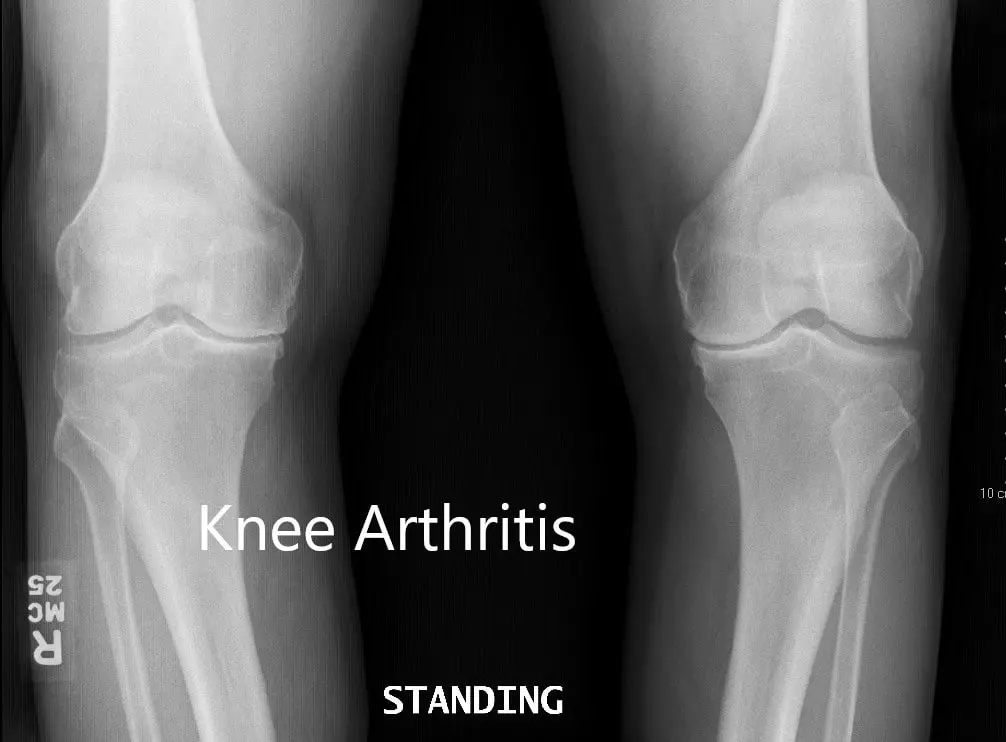

Her imaging studies of both the knee revealed severe tricompartmental osteoarthritis. Considering her lifestyle limiting knee pain, she was advised bilateral custom total knee replacement. Risks, benefits, and alternatives were discussed with the patient at length. She agreed to go ahead with a bilateral custom knee replacement.

Preoperative X-ray showing the AP view of both knees

Preoperative X-ray showing the AP view of both knees.